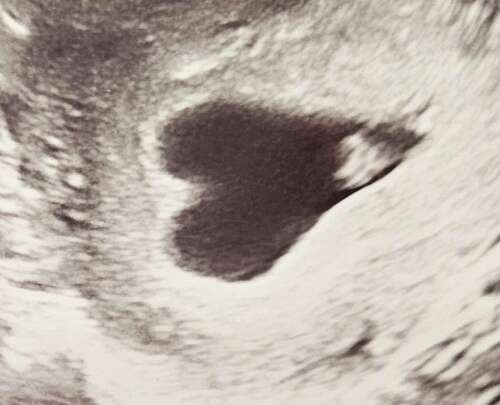

Hier ook een kloppend hartje! Ik ben teruggezet naar 6+1. Wel een hartvormige baarmoeder. De verloskundige was er niet zo ongerust over, wel meer kans op vroeggeboorte of een keizersnede. Ik laat het even bezinken en voor nu is het een mooi plaatje zo 馃グ